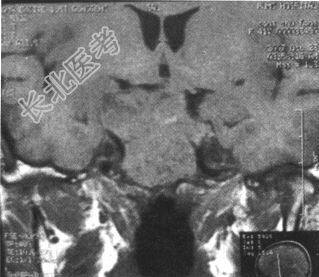

鞍区MRI如下图。